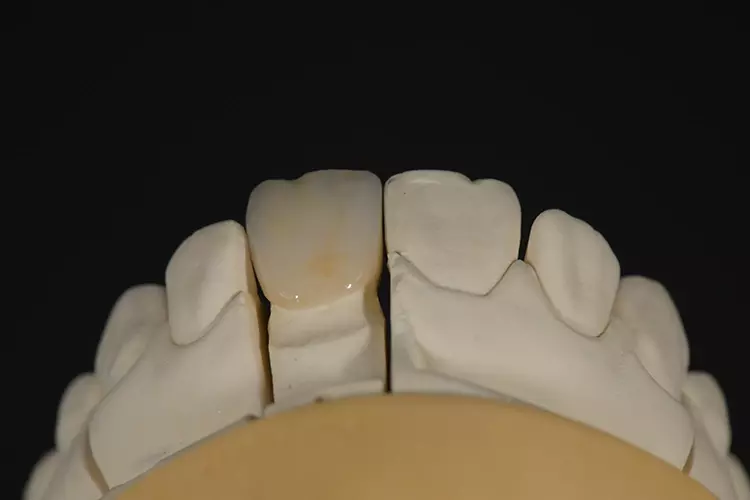

Die Auswahl des Materials für die definitive Krone wurde in Rücksprache mit dem Zahntechniker getroffen. Sie erfolgte nach der Herstellung der Arbeitsmodelle, der Beurteilung der Platzverhältnisse, der Stumpffarbe und der definierten Zielfarbe. Aufgrund des verfärbten und devitalen Zahnes und zur Vermeidung des „Grauschleiers“ galt es, ein Material mit weniger Transluzenz als Lithiumdisilikat zu verwenden.

Es sollte ein Zirkonoxidmaterial mit hochästhetischen Eigenschaften zum Einsatz kommen. Die Wahl fiel auf IPS e.max ZirCAD Prime, ein Werkstoff der zwei Zirkoniumdioxid-Rohstoffe kombiniert: im Dentinbereich ein 3Y-TZP-Zirkonia mit hoher Festigkeit (1.200 MPa Biegefestigkeit) und im Schneidebereich ein transluzenteres 5Y-TZP-Zirkonia (650 MPa Biegefestigkeit). Der stufenlose Farb- und Transluzenzverlauf in den Materialscheiben ist ein zusätzlicher Vorteil für derartige Restaurationen im sichtbaren Bereich.

Zur Realisierung eines möglichst naturgetreuen Behandlungsergebnisses wurde labial ein minimales Cut-back und eine anschließende individuelle Schichtung mit der Verblendkeramik IPS e.max Ceram durchgeführt (Mikroveneering) (Abb. 30–33). Damit der verfärbte Zahnstumpf unter der neuen Zirkonkrone nicht mehr sichtbar ist, wird bei transluzentem Zirkoniumdioxid im Weißzustand auf der Innenseite des Gerüstes ein Opakerliquid aufgebracht. Dieses Liquid trägt nicht auf, da das Material in den Werkstoff eindringt und das Zirkongerüst an den gewünschten Stellen von innen blickdicht, sprich opak, wirken lässt (Fa. BriegelDental) (Abb. 34 und 35).